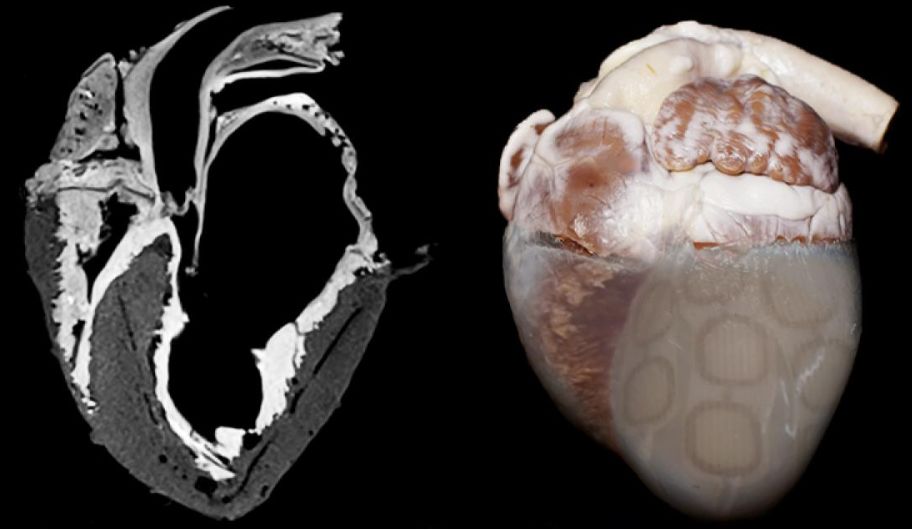

▲图 | “生物机械混合心脏”(来源:AAAS)

这种被称为 “生物机械混合心脏” 的仿生心脏极其接近真实生物心脏,它的构成一部分是用化学方法保存的活体心脏组织,另一部分是帮助心脏输送血液的人造基体。

如下图所示,心脏下部的肌肉组织被替换成了人造心肌,这种人造心肌是一个柔软的、由 TissueSil 粘合剂组合起来的人造模型,类似汽泡纸。

▲图 | 心脏下部的肌肉组织被替换成了人造心肌(来源:MIT News)

人造肌肉的方向模拟心脏天然的纤维形态,研究人员可以远程充气,通过挤压心脏内部来模拟真实的心脏跳动方式和血液循环。